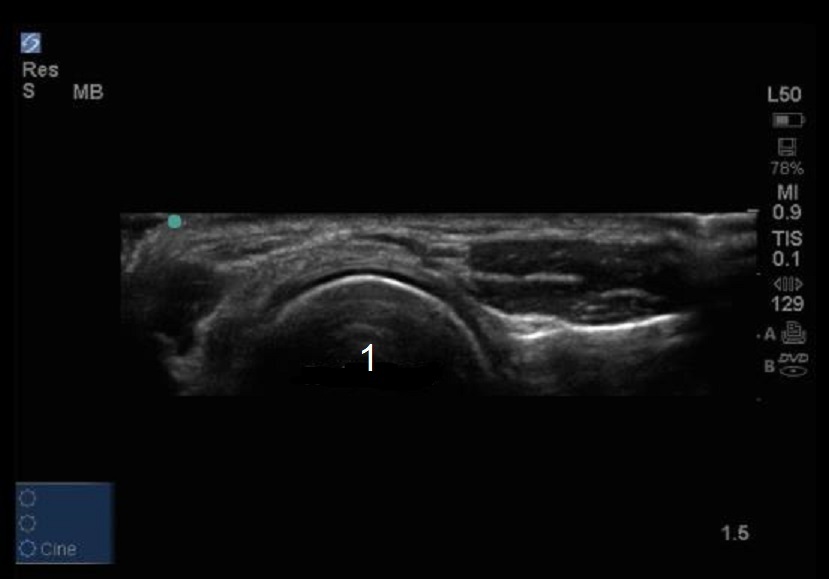

軟骨のある肘橈骨頭の横断画像

橈骨頭